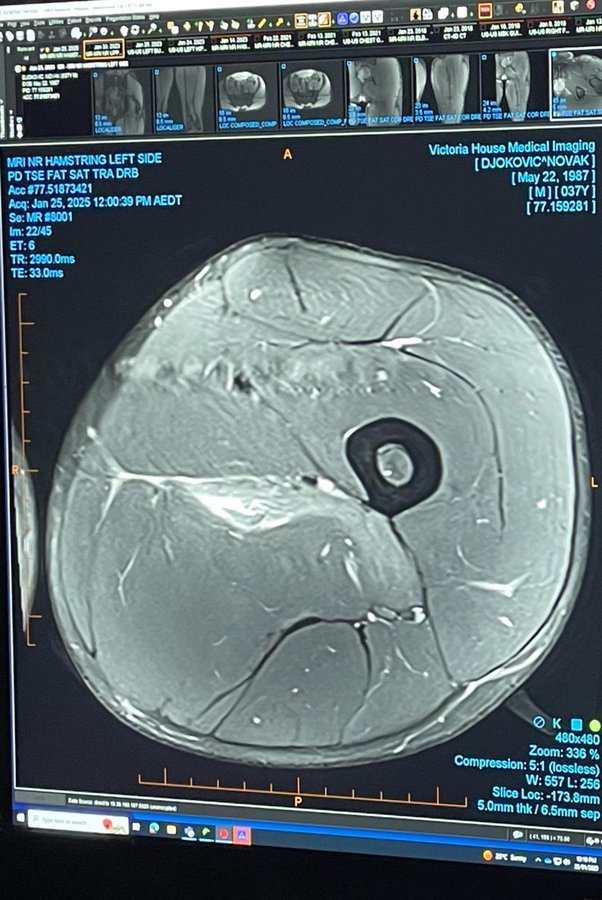

Новак Джокович показа снимка от ядрено магнитен-резонанс на контузеното си бедро, което го извади от участие на Australian Open.

"Реших да оставя това тук за всички "експерти" по спортна медицина", написа Джокович в своя профил в X.